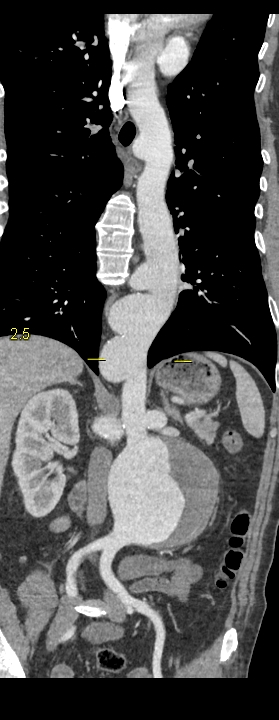

Figurile 2, 3 și 4: reconstrucţii oblic coronale aortă postoperator

Discuţie caz nr 104: Pacient în vârstă de 51 de ani este descoperit cu multiple dilatații anevrismale de tip sacular la nivelul aortei toracice și abominale precum și la nivelul arterei subclavii stângi și la nivelul arterelor renale; în plus, anevrismul de aorta abdominală infrarenal e parțial trombozat cu diametrul de 8 cm. Este operat atât supra cât și subdiafragmatic, cu menținerea dilatației anevrismale a arterei subclavii stângi și a unor creșteri de calibru a aortei la nivelul crosei și la limita dintre aorta toracică și cea abdominală.